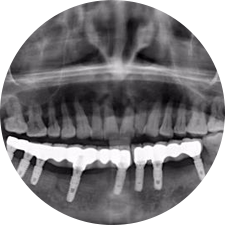

口腔種植是將人工牙根通過手術(shù)植入牙骨內(nèi),獲得牙槽骨牢固的支持,通過特殊的裝置和方式連接牙修復體,獲得與天然牙功能、結(jié)構(gòu)以及美觀相似的效果。

河北惟德口腔醫(yī)院擁有國內(nèi)豐富的半口/全口、即刻負重種植案例,十八年案例跟蹤分析,總結(jié)梳理出的各種不同類型的種植案例,Nobel種植體系針對半口/全口缺牙患者,通過4-8顆種植體可快速達到牙齒重建,不僅植入種植體較少,節(jié)省費用,手術(shù)時間更短。

術(shù)前患者CBCT口掃1:1三維重建,模擬手術(shù)過程及預測術(shù)后治療效果,確定每顆植體植入的適合的種植位點、深度及角度,有效避免損傷頜骨重要解剖結(jié)構(gòu),提高手術(shù)準確度與安全性。

Noble口腔種植體系基本不受年齡限制,適用于缺牙修復,也適用于牙槽骨萎縮、骨質(zhì)疏松、高血壓、糖尿病、超高齡的患者,即種即用,只需少量微小種植體,便可輕松微痛快速重建全口咬合,特殊力學設(shè)計,針對許多年紀較大,骨質(zhì)條件差,身體耐受力差的缺牙老人也能完成“即種即用”,受到廣泛好評。

惟德口腔種植體系是以患者感受為中心,取代傳統(tǒng)種植牙手術(shù)需要翻瓣、打孔、縫合,術(shù)前、術(shù)中、術(shù)后的繁復流程,采用3D導航微創(chuàng)準確種植技術(shù),通過數(shù)字化CAD/CAM掃描技術(shù)獲得缺牙患者口腔數(shù)據(jù),以數(shù)據(jù)為基礎(chǔ)重建口腔模型進行模擬種植。

術(shù)前將患者口內(nèi)的CBCT數(shù)據(jù)及咬合關(guān)系上傳到計算機中,建立1:1三維重建,模擬手術(shù)過程及預測術(shù)后治療效果,找出較佳種植位點、深度及角度,獲取實際種植體在頜骨內(nèi)的具體三維位置,有效避免損傷頜骨重要解剖結(jié)構(gòu),大大降低手術(shù)風險,提升種植成功率。